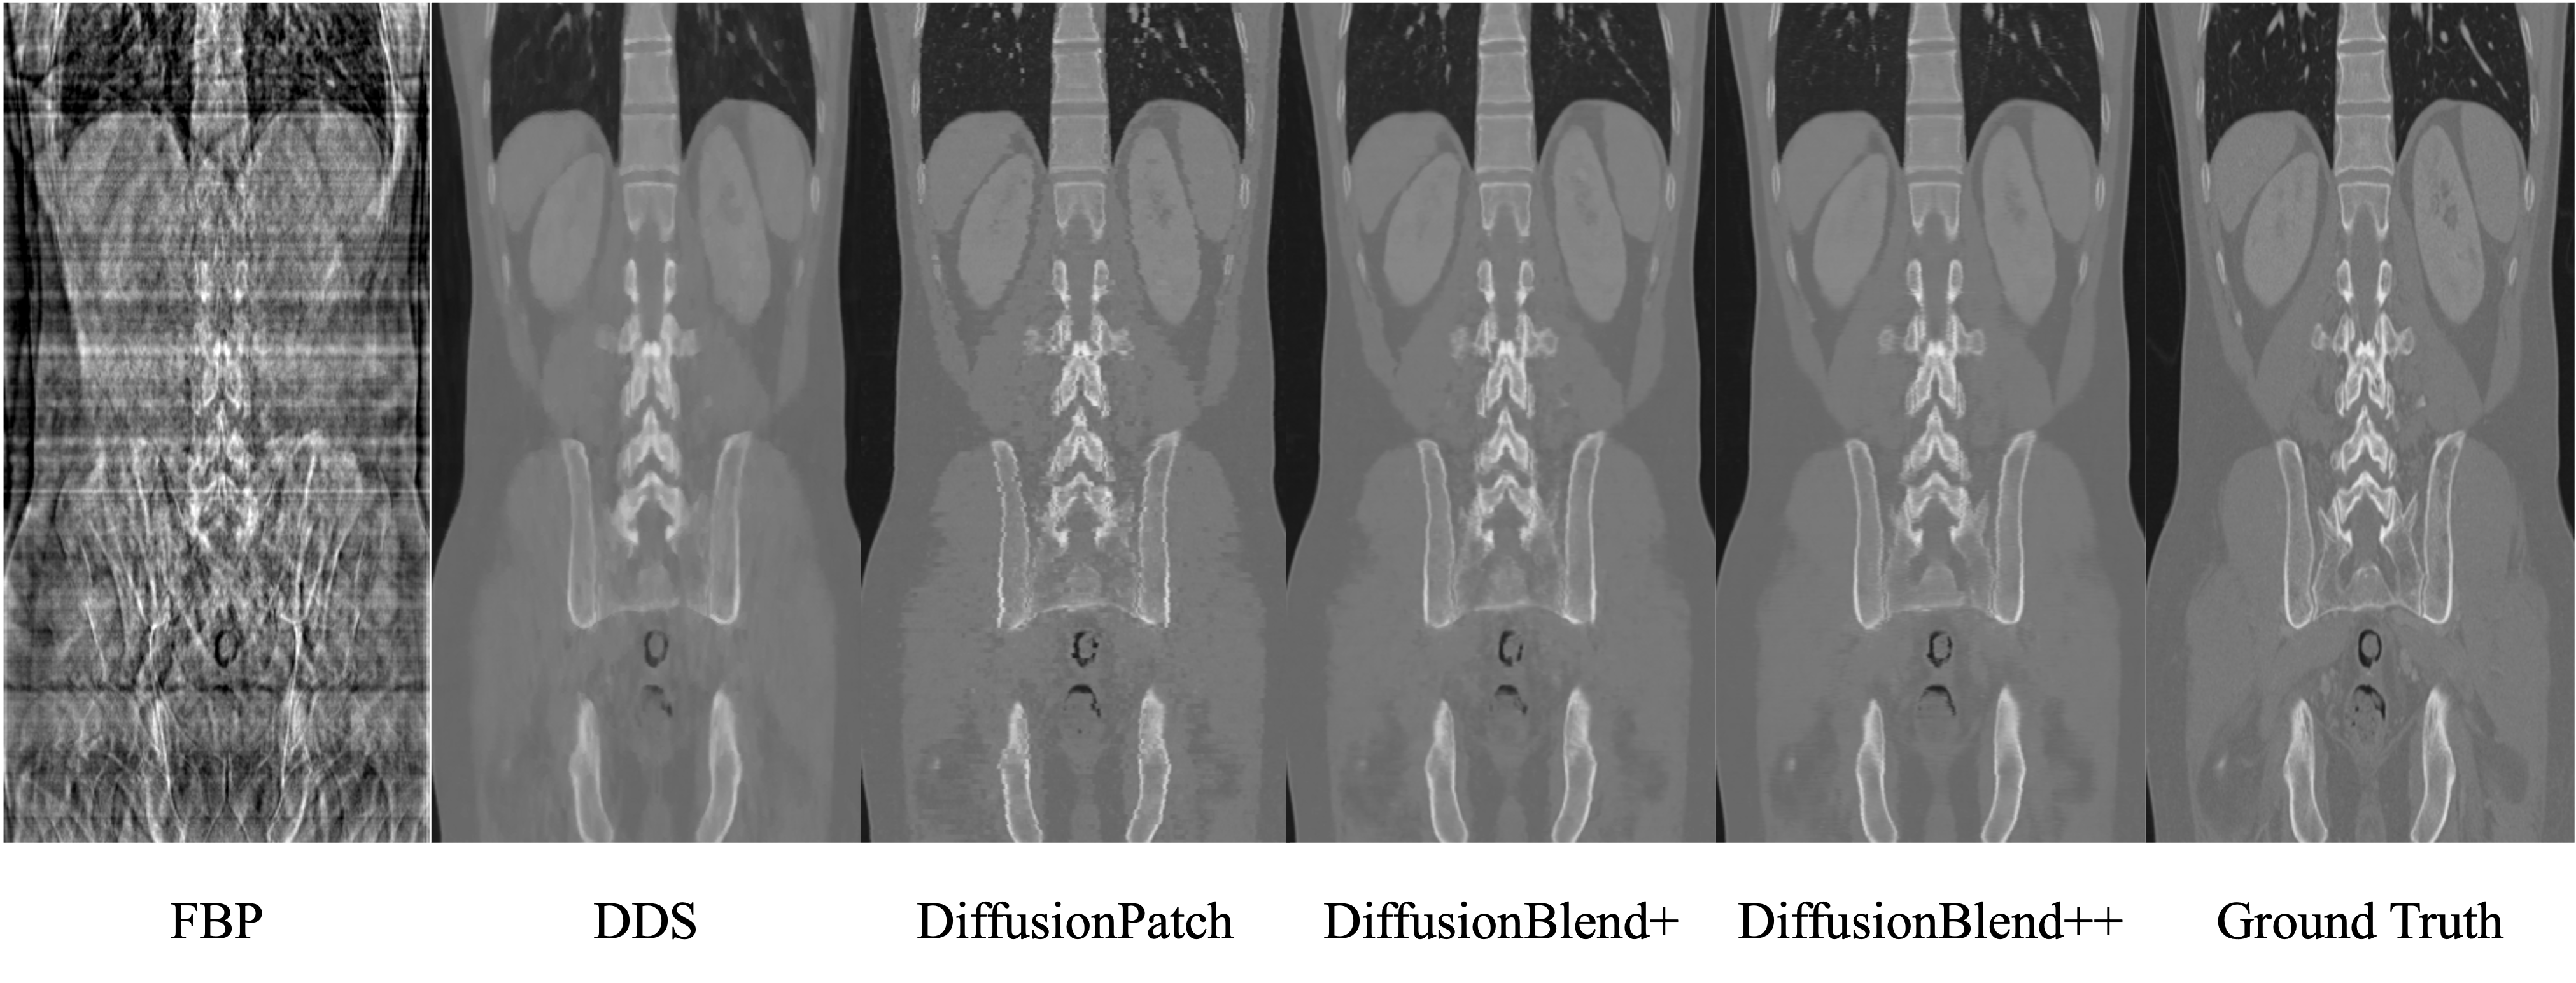

Refer to caption

Figure 4: Results of CT reconstruction with 8 views on AAPM dataset, coronal view. DiffusionPatch refers to Algorithm 1 with the same partition for every timestsep, and DiffusionBlend+ refers to Algorithm 1 only with partitions of adjacency slices.

We demonstrate that DiffusionBlend++ learns the 3D prior internally, and achieves consistency and smoothness between 2D axial-plane slices without any external regularizations. In Table 5, we present the total variation (TV) value of the reconstructed images of different reconstruction algorithms on the test set of AAPM dataset, given by 1C×W×H𝐃z(x)11𝐶𝑊𝐻subscriptnormsubscript𝐃𝑧𝑥1\frac{1}{C\times W\times H}||\mathbf{D}_{z}(x)||_{1}, where x𝑥x is the image, 𝐃zsubscript𝐃𝑧\mathbf{D}_{z} is the total variation operator in z𝑧z direction, and C𝐶C, W𝑊W, H𝐻H are number of channels, width, and height. We find that both DiffusionBlend++ and DDS have TV less than the ground truth image, which implies that the reconstructed images are smooth in the z direction. However, we observe that DDS over-smooths the images as demonstrated in Fig. 4, which is represented by a much lower TV value than the ground truth. On the other hand, DiffusionBlend++ has smoothness level close to the ground truth without sacrificing sharpness of images.

We demonstrate that both the adjacency-slice blending and the cross-slice blending module are instrumental to a better reconstruction quality. Table 6 demonstrates the effectiveness of adding blending modules to the reverse sampling. Given the pretrained diffusion prior over slice patches, we observe that adding the adjacency-slice blending module improves the PSNR over a fixed partition by 1.17dB, and adding an additional cross-slice blending module further improves the PSNR by 1.63dB. Fig. 4 demonstrates that adding the cross-slice blending module removes artifacts and recovers sharper edges.